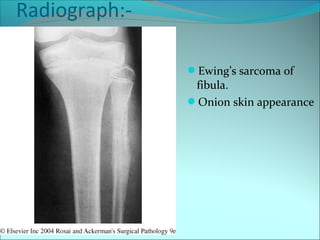

Radiograph:-

Ewing’s sarcoma of

fibula.

Onion skin appearance

• #42 Roentgenogram of Ewing tumor shows a destructive lesion with periosteal new bone formation giving rise to an onionskin appearance